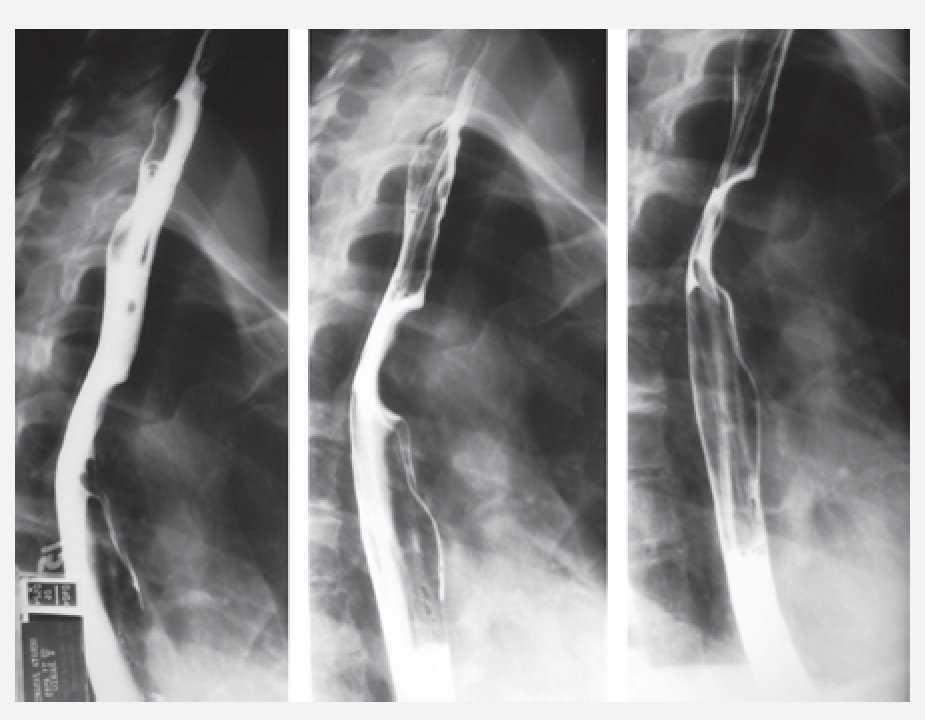

Mujer de 34 años sin antecedentes personales patológicos, quien consulta con historia de 3 meses de evolución de disfagia progresiva. Estudio baritado esofágico reveló compresión extrínseca en tercio medio (Imagen 1). La endoscopia alta mostró una lesión que ocluía 50% de la luz esofágica con mucosa intacta. La tomografía axial computada con contraste esofágico reveló una lesión intramural, no adherida a planos adyacentes a nivel de la pared esofágica lateral derecha en el tercio medio, cercano al cayado aórtico (Imagen 2). A la paciente se le realizó enucleación toracoscópica con abordaje lateral derecho de tumoración esofágica en tercio medio sin complicaciones (Fotos 1 y 2). El informe histopatológico reportó GIST (Gastrointestinal Stromal Tumor) esofágico CD117 (+). Estudio contrastado de control sin estrecheces ni escape. Fue dada de alta al cuarto día posoperatorio.

Imagen 1. Estudio de contraste del esofágico. Evidencia de compresión extrínseca en tercio medio.